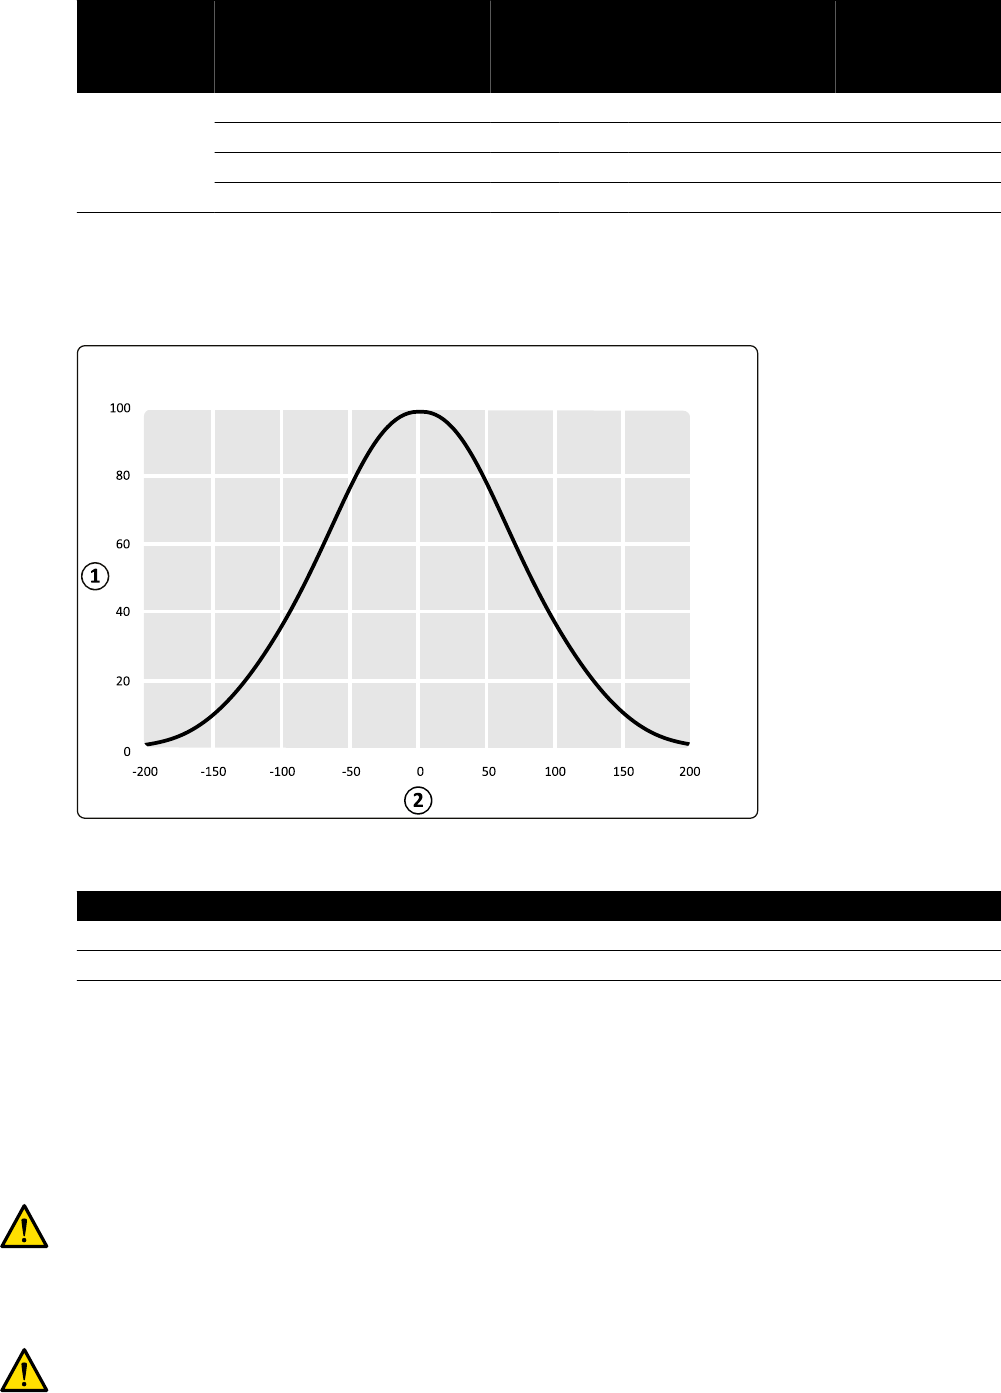

dawki (%) 100 130 145 170 200 240 280 330

Rozmiar pola